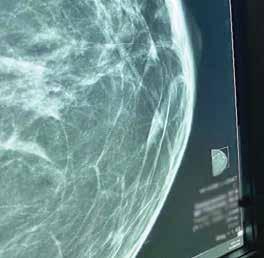

El cáncer de seno es el cáncer más comúnmente diagnosticado, y la primera causa de muerte, en mujeres. El Colegio Americano de Radiología recomienda el cernimiento con mamografía o tomosíntesis a partir de los 40 años para aquellas pacientes con un riesgo promedio para cáncer. El radiólogo especialista juega un rol importante en la detección temprana de esta condición utilizando varias modalidades diagnósticas. El cernimiento se hace mediante mamografía o su modalidad asociada conocida como tomosíntesis. La tomosíntesis tiene mayor sensibilidad y especificidad que la mamografía regular y delimita con más detalle los bordes en lesiones identificadas. También, tenemos la mamografía con contraste que es otra excelente herramienta para evaluar lesiones en tejidos densos utilizando un medio de contraste a base de Iodo.

Mamografía

La mamografía es una modalidad de rayos x. La técnica consiste en obtener dos imágenes comprimiendo cada seno, se obtienen vistas craneocaudal y mediolateral oblicua. El seno se compone de grasa y tejido mamario glandular. Mientras más tejido glandular mamario, más denso (o blanco) se ve el seno en la mamografía. La sensibilidad de la mamografía para detectar cáncer de seno varía entre un 70% a un 85% dependiendo de la densidad.

Tomosíntesis

La tecnología de la mamografía ha seguido evolucionando y la Food and Drug Administration (FDA) en el 2011 aprobó una modalidad de mamografía más sofisticada llamada tomosíntesis. Con ésta se obtiene la mamografía 2D tradicional y además se realiza una evaluación tridimensional (3D). La tecnología utiliza una angulación en arco que toma múltiples imágenes en dos proyecciones (frente y de perfil) del seno. Las imágenes obtenidas son procesadas brindando al radiólogo la posibilidad del análisis en tres dimensiones del seno.

La tomosíntesis tiene mayor sensibilidad y especificidad en la detección de imágenes en las diferentes variedades de densidad mamaria; sobre todo en el tejido mamario fibroglandular y heterogéneamente denso. Esta modalidad disminuye hasta un 17% la llamada al paciente para vistas adicionales. Y puede aumentar la detección de cáncer hasta un 53%. También delimita mucho mejor los bordes de las lesiones que la mamografía tradicional.

En la mamografía o tomosíntesis podemos detectar microcalcificaciones, masas, asimetrías o distorsiones. Algunas microcalcificaciones basadas en su morfología irregular pueden estar asociadas a la presentación más temprana de cáncer de seno, carcinoma ductal in situ (DCIS), y la mamografía o tomosíntesis son la mejor modalidad para detectarlas.